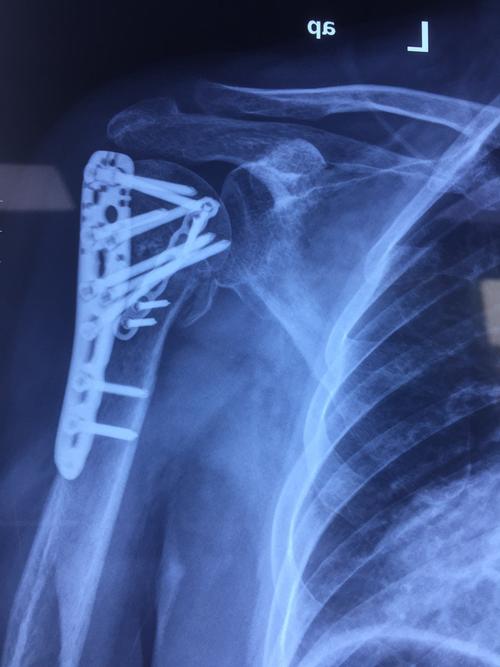

左肱骨近端骨折图片

左肱骨近端骨折图片,股骨近端骨折

肱骨近端骨折

左侧肱骨近端骨折

肱骨近端骨折图片

肱骨近端骨折内固定

肱骨近端骨折术后

肱骨近端骨折钢板